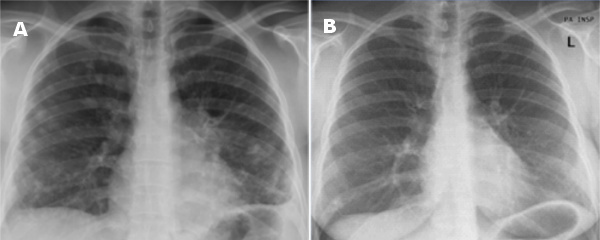

A 39-year old female presented with exertion dyspnoea, non-productive cough, chest pain, asthenia and anorexia. These symptoms started 1 month prior to admission. The chest X-ray showed multiple bilateral nodular shadows (figure 1A).

Figure 1 Left (A) Chest X-ray at presentation showing multiple bilateral nodular shadows;

right (B) Chest X-ray one year after presentation showing a reducition of the interstitial lesions

At follow-up, spirometry and diffusing capacity remained normal as well as blood chemistry and angiotensin converting enzyme. A chest roentgenogram performed one year later showed a reduction of the interstitial features (figure 1B). High resolution CT revealed residual fibrotic changes at the sites where previously the bigger nodules had been (figure 2 right).